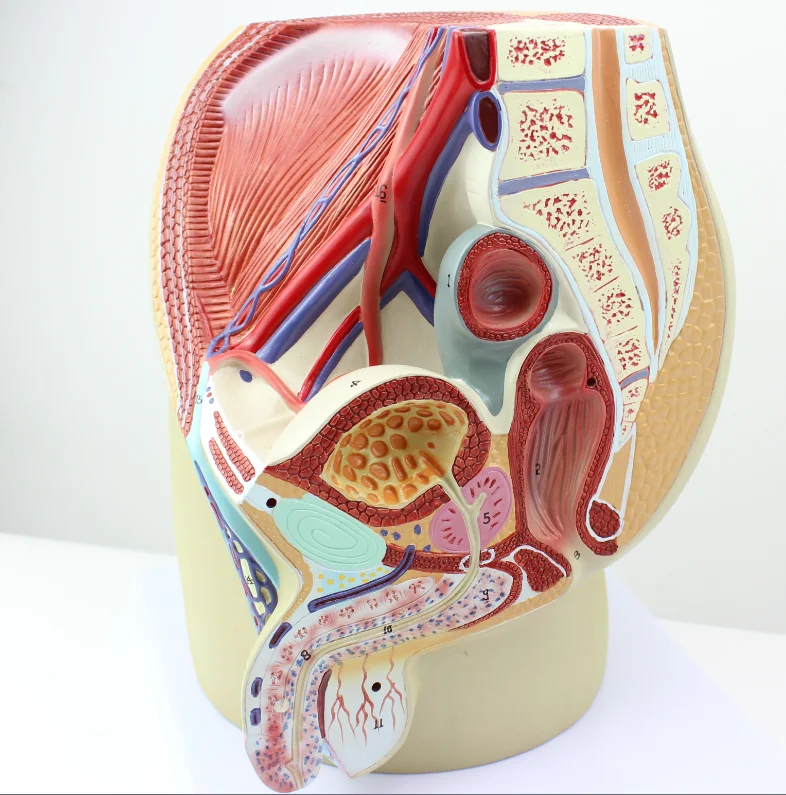

Раздел: Экспозиция интеллекта